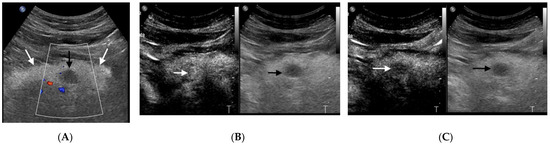

3.1. Pancreatic Ductal Adenocarcinoma